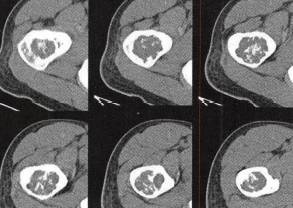

图1右股骨内生软骨瘤

B.CT平扫软组织窗见右股骨干骺端中心性类圆形低密度肿块,边界清晰,其中央见斑点状、斑片状高密度钙化,骨旁肌间隙清晰,未见异常软组织肿块影;